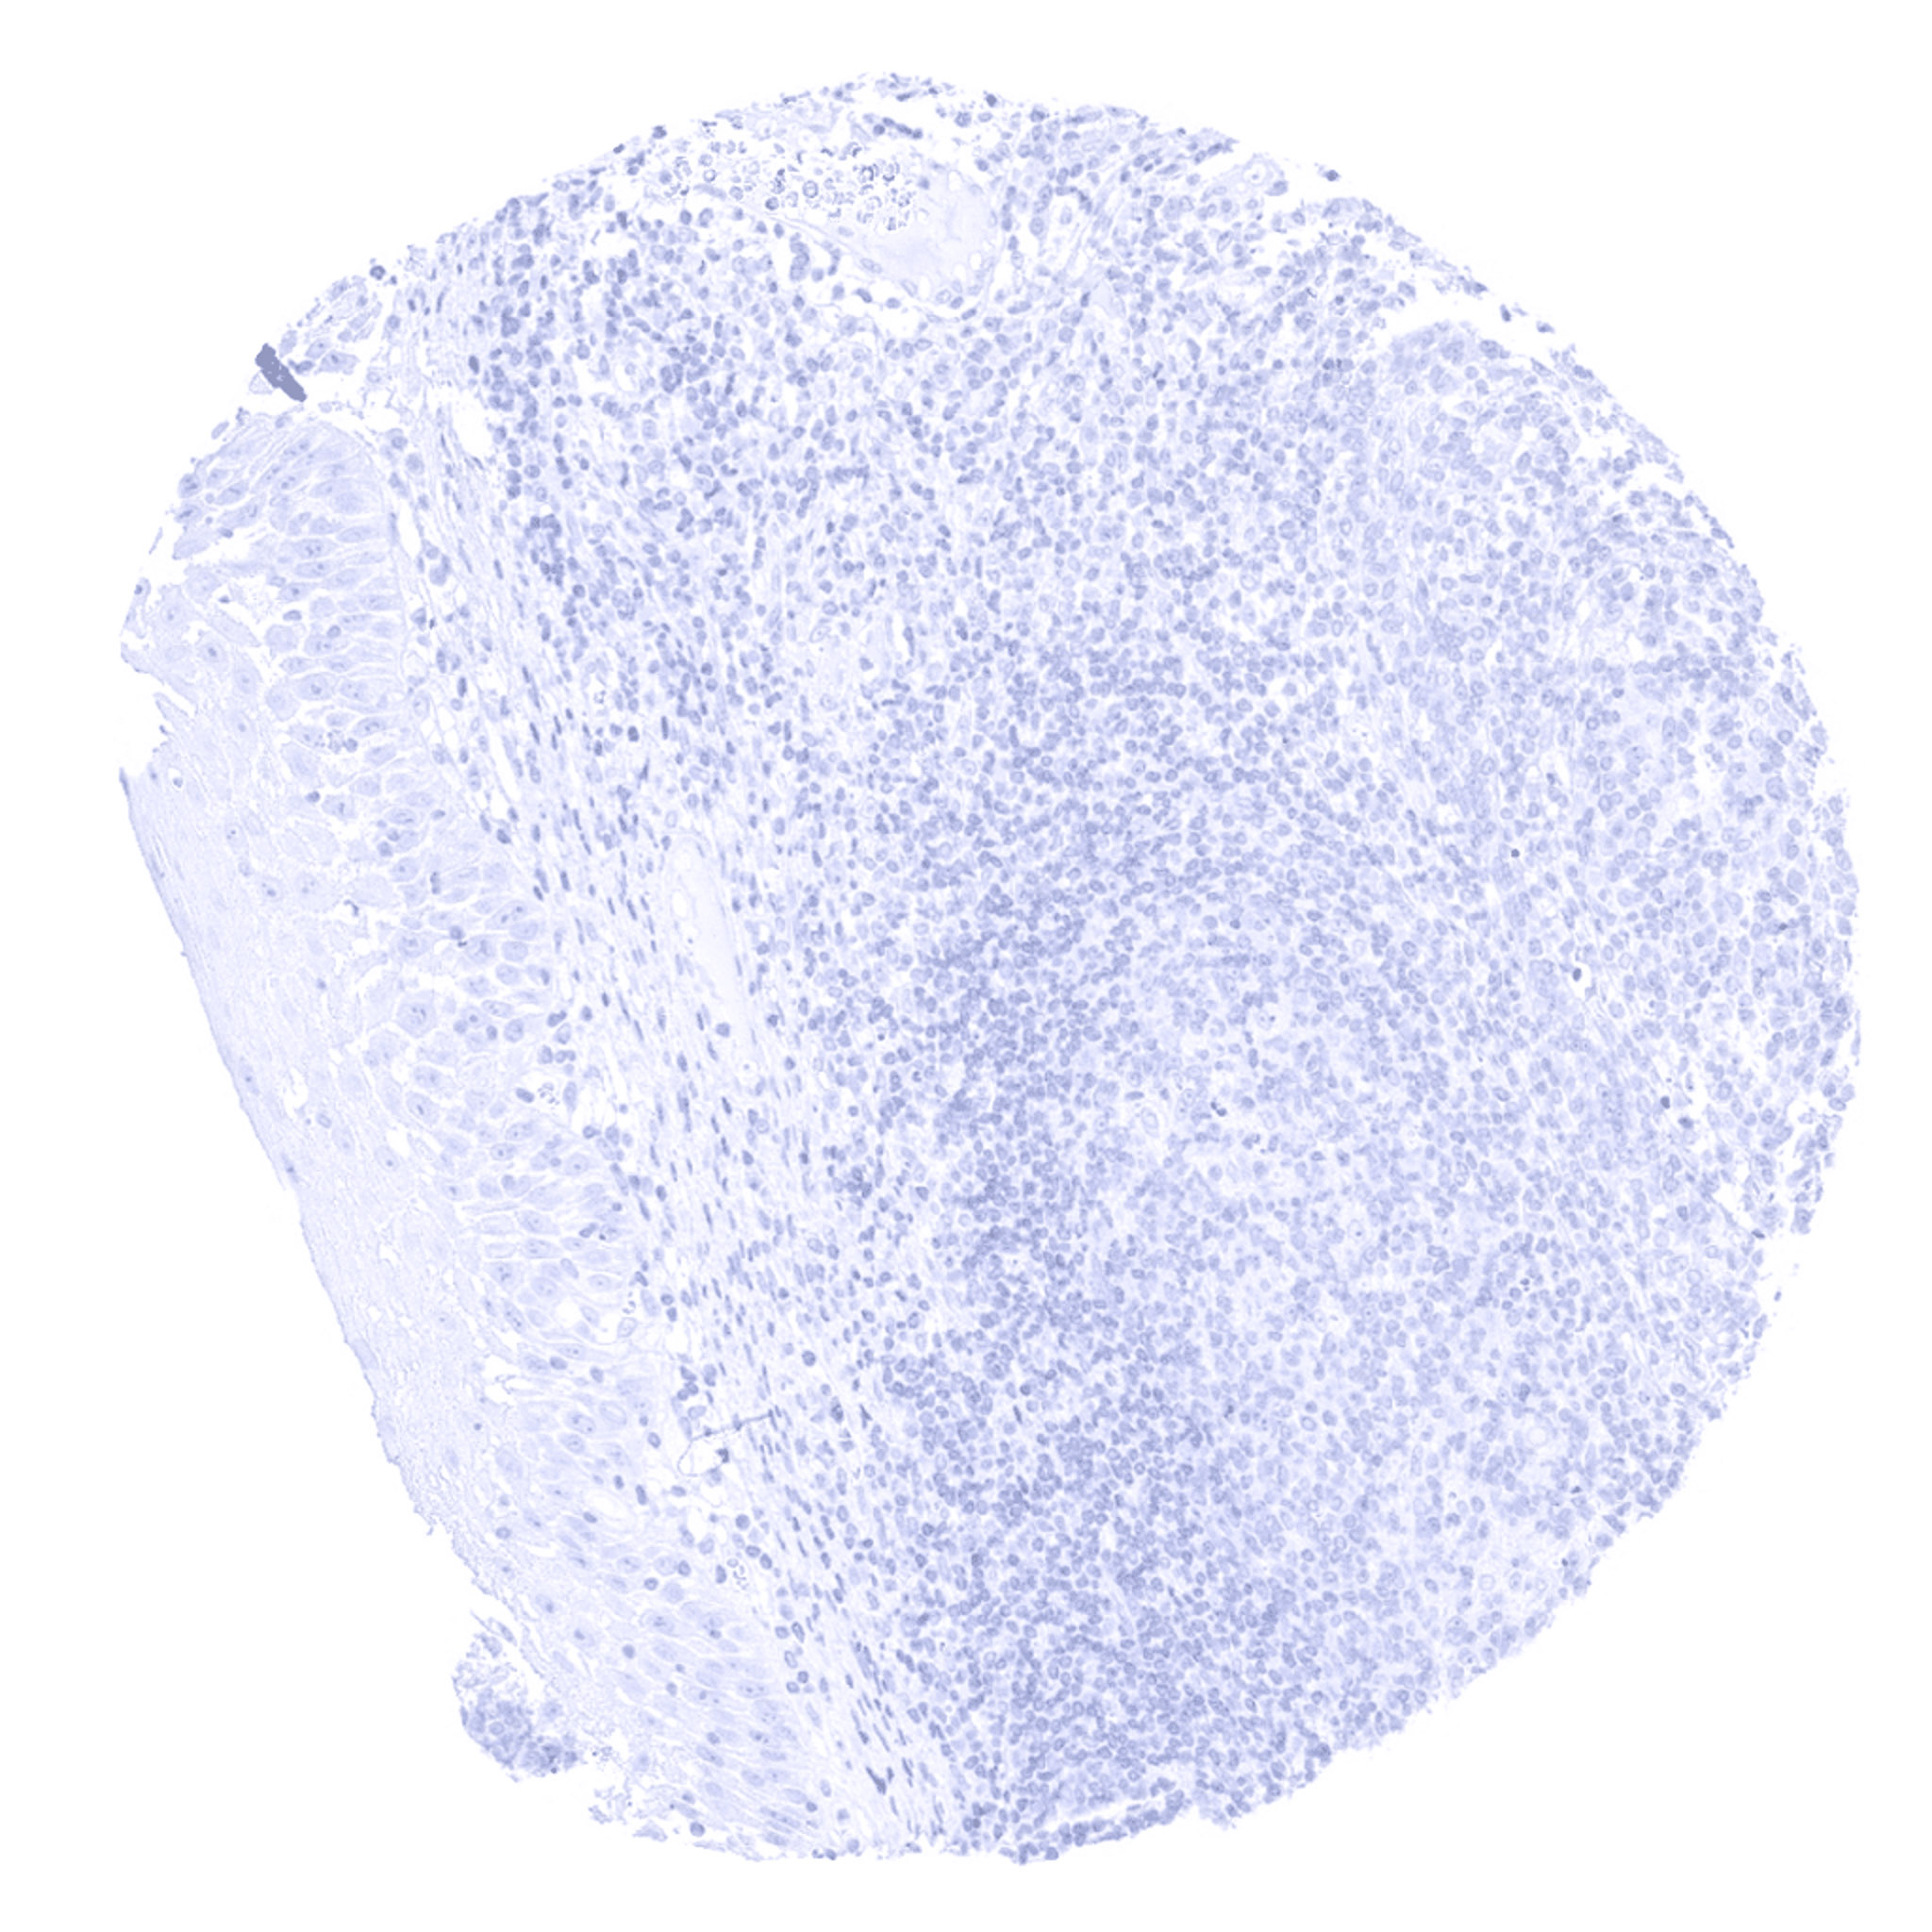

Tonsil